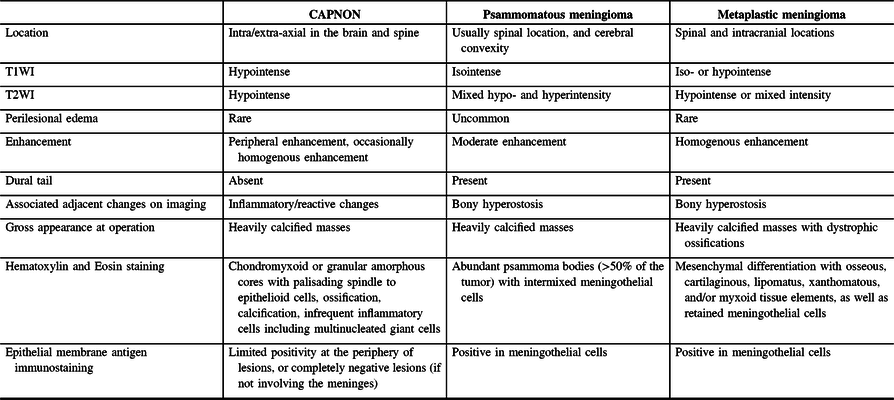

Radiographic differential diagnoses of skull base CAPNONs should include calcified meningioma subtypes, chordoma, chondrosarcoma, schwannoma, granulomatous lesions, and other inflammatory lesions.Reference Bertoni, Unni, Dahlin, Beabout and Onofrio13 The meningioma subtypes, in particular psammomatous and metaplastic meningiomas, should be the top differential diagnoses for a calcified lesion located at the skull base. CAPNONs are often mistaken as calcified meningiomas until a pathological diagnosis is made after surgical intervention.Reference Aiken, Akgun, Tihan, Barbaro and Glastonbury3,Reference Alshareef, Vargas, Welsh and Kalhorn4,Reference Garen, Powers, King and Perot7–Reference Shrier, Melville and Millet10 However, there are some subtle differences in the imaging characteristics between CAPNONs and calcified meningiomas (Table 2). First, the lack of a dural tail on CAPNONs can help distinguish them from calcified meningiomas. Second, CAPNONs are usually hypointense on T1WI and T2WI and perilesional edema is rare.Reference Aiken, Akgun, Tihan, Barbaro and Glastonbury3,Reference Barber, Low, Johns, Rich, MacDonald and Jones5 Additionally, the majority of cases of CAPNON demonstrate a peripheral enhancement pattern in contrast to psammomatous and metaplastic meningiomas.Reference Barber, Low, Johns, Rich, MacDonald and Jones5 Of note, our right CPA CAPNON is vividly enhancing with contrast, similar to a previous case reported by Alshareef and colleagues.Reference Alshareef, Vargas, Welsh and Kalhorn4 In contrast, psammomatous meningiomas are often isointense on T1WI and have mixed hypo- and hyperintensity on T2WI, with moderate homogeneous enhancement with contrast. Similar to CAPNONs, perilesional edema is uncommon. Additionally, psammomatous meningiomas have a predilection for the spine and cerebral convexity.Reference Liu, Lu and Peng25 Metaplastic meningiomas tend to be iso- or hypointense on T1WI, hypointense or of mixed intensity on T2WI, with homogenous enhancement and rare perilesional edema.Reference Caffo, Caruso, Barresi and Tomasello26,Reference Tang, Sun and Chen27

Table 2: Comparisons of CAPNON, psammomatous meningioma, and metaplastic meningioma

Pathologically, CAPNONs are distinctly different from grossly calcified, psammomatous meningiomas and metaplastic meningiomas. CAPNON is typically composed of the following components: (1) chondromyxoid cores containing amorphous to fibrillary materials; (2) peripheral palisading of spindle to epithelioid cells; (3) calcifications and ossifications; and (4) foreign-body reaction with multinucleated giant cells.Reference Qian, Rubio and Powers23 Despite high variations in these morphological components, the chondromyxoid cores with calcification seem to be a principal constituent of CAPNON. On the other hand, psammomatous meningiomas consist of abundant psammoma bodies (more than half of the tumor) with intermixed meningothelial cells.Reference Liu, Lu and Peng25 Metaplastic meningiomas are characterized by mesenchymal differentiation including osseous, cartilaginous, lipomatus, xanthomatous, and/or myxoid tissue elements, with retained meningothelial cells in nonmetaplastic areas.Reference Caffo, Caruso, Barresi and Tomasello26,Reference Tang, Sun and Chen27 EMA immunostaining, a routinely used marker for meningiomas, is positive largely in the retained meningothelial cells in metaplastic and psammomatous meningiomas. In contrast, CAPNONs have limited EMA positivity that is often linear in distribution and typically seen at the periphery of the amorphous cores or the tissue edge of CAPNONs,Reference Aiken, Akgun, Tihan, Barbaro and Glastonbury3 which may be reflective of the meningeal involvement in the stroma rather than the constituent of CAPNONs. In the 24 reviewed cases of skull base CAPNONs, EMA immunostaining was positive with or without specified distribution in 6 cases (including our 2 cases),Reference Blood, Rodriguez, Nolan, Ramanathan and Desai14,Reference Fletcher, Greenlee, Chang, Smoker, Kirby and O’Brien15,Reference Kerr, Borys, Bobinski and Shahlaie17,Reference Wisniewski, Janczar, Tybor, Papierz and Jaskolski24 but negative in 2 cases,Reference Hodges, Karikari and Nimjee16,Reference Nussbaum, Hilton and Defillo20 and not mentioned in the remaining 16 cases. We speculate that EMA is usually negative in CAPNONs without the meningeal involvement or focally positive in CAPNONs with the meningeal involvement, and its positivity is limited to the meningothelial cells entrapped in CAPNON lesions. Therefore, EMA is a useful pathological marker to differentiate CAPNONs from calcified psammomatous or metaplastic meningiomas (Table 2).